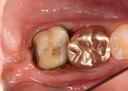

Gary Umeda #31 pre-op

Gary Umeda #31 caries removal

Gary Umeda #31 prep